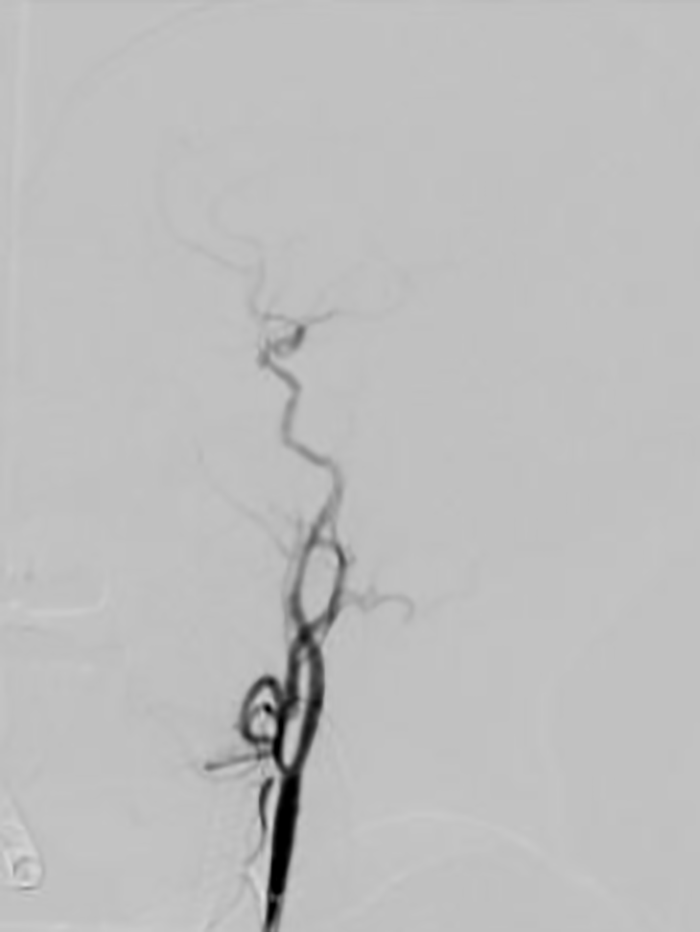

经过两个小时的抢救,患者血管全部再通,手术取得成功!

▲患者术后脑血管完全再通